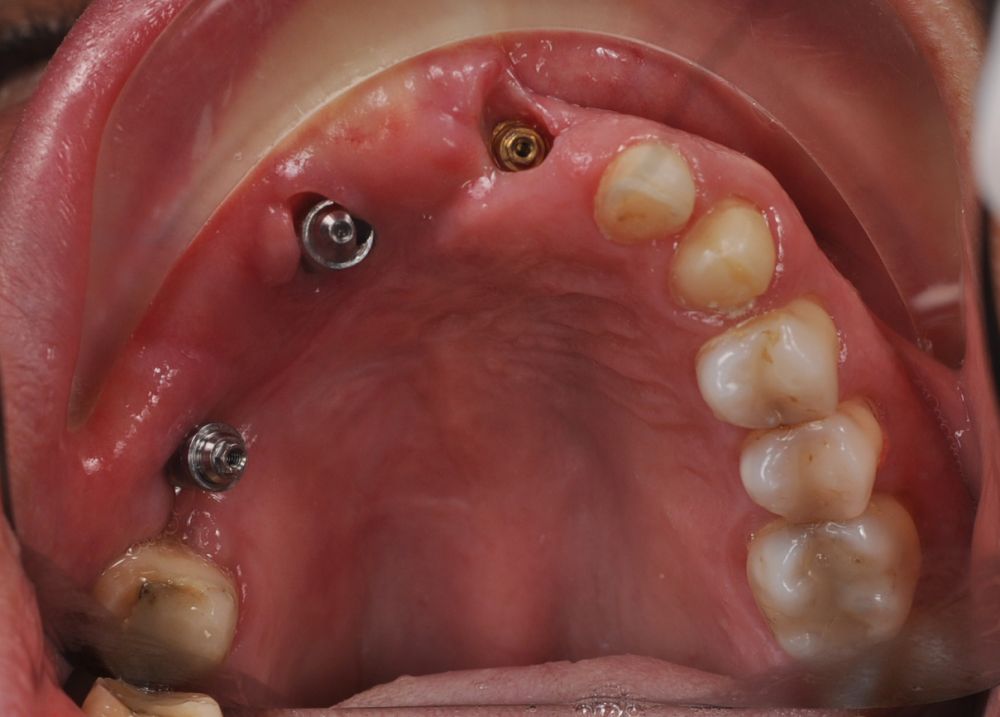

Una vez finalizada la radioterapia, la paciente se encontraba libre de enfermedad. Por lo que se procedió a la restauración definitiva implantosoportada. Tras la segunda fase, se colocaron dos pilares transepiteliales Multiunit Ò rectos y un pilar Multunit Ò angulado de 17º (Figura 10).

Finalizado el tratamiento oncológico y confirmada la ausencia de enfermedad activa, se procedió a la segunda fase quirúrgica con la colocación de pilares transepiteliales Multiunit®. La integración de los implantes cigomáticos y del implante endoóseo fue satisfactoria, observándose estabilidad clínica y ausencia de signos de periimplantitis.